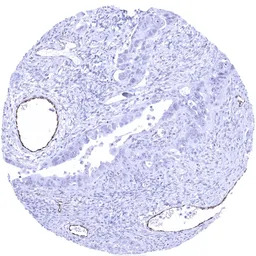

IHC-P analysis of human ovary serous high grade carcinoma tissue section using GTX04412 VWF antibody [MSVA-521R] HistoMAX.

Serous high grade carcinoma showing distinct endothelial VWF staining in a subset of intratumoral vessels.